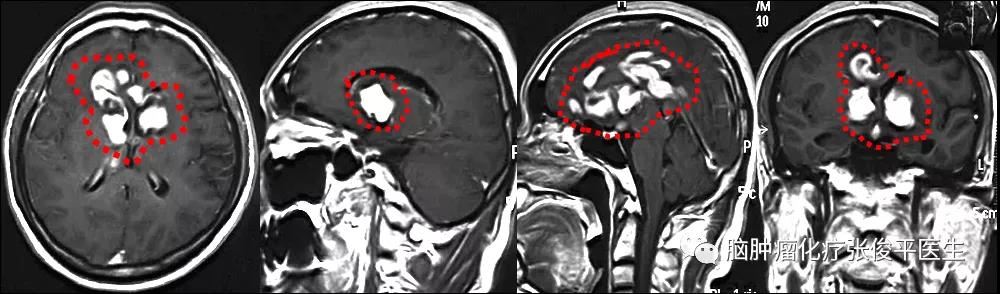

2010年5月,患者无明显诱因出现疲倦,睡眠增多,易疲劳,记忆力下降,且伴有头部发胀,不伴有头痛头晕,不伴有恶心呕吐,无癫痫发作等。在当地医院行头颅核磁示:双侧基底节区及岛叶占位(如图1)。

图1. 2010-06-01核磁,发现双侧基底节区及岛叶占位。